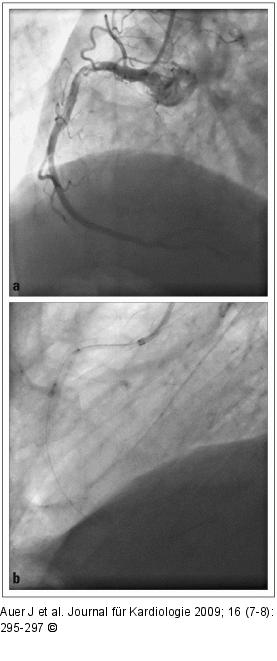

Abbildung 2a-b: TIMI-II-Fluss TIMI-II-Fluss der RCA (a) und Einführen des Katheters in die RCA (b). |

Abbildung 2a-b: TIMI-II-Fluss

TIMI-II-Fluss der RCA (a) und Einführen des Katheters in die RCA (b). |